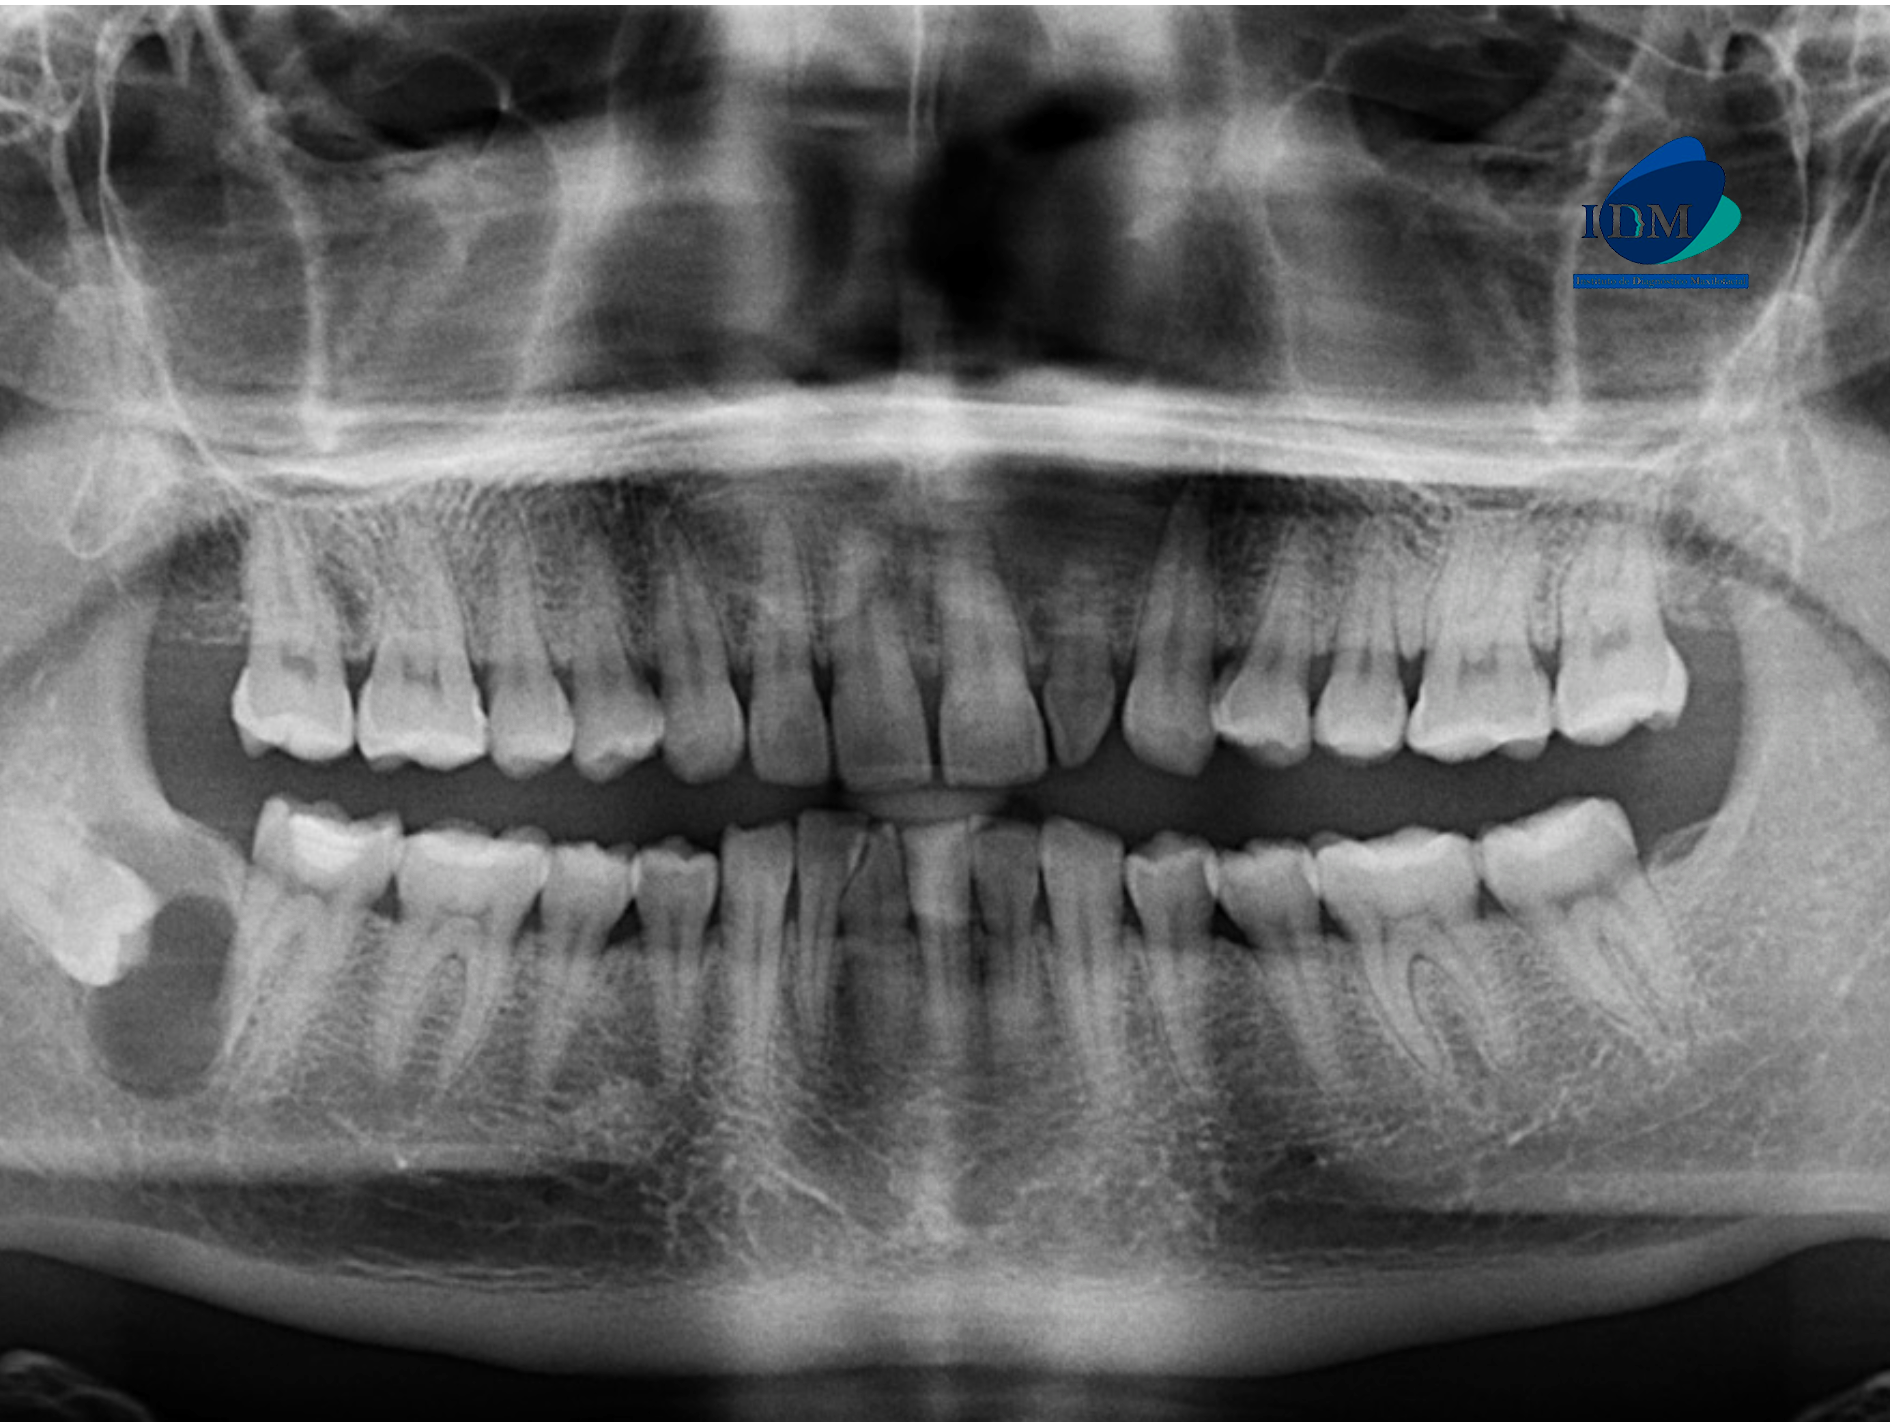

Paciente masculino de 37 años de edad, es referido al Instituto de Diagnóstico Maxilofacial – IDM para evaluación de zona posterior derecha.

En la radiografía panorámica (Figura 1), se aprecia mineralización parcial de los procesos estilohioideos, neumatización alveolar de senos maxilares, imagen radiolúcida pericoronaria en pieza 48, de limites definidos, bordes corticalizados, que se extiende hasta distal de pieza 47.

Radiografia Panorámica